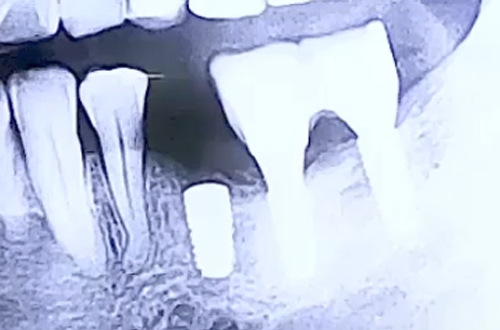

약해진 잇몸뼈에 식립한 작은 어금니 임플란트 사례

AFTER

약한 잇몸뼈에 맞춰 그대로 얇은 임플란트를 사용하면 어금니의 기능을 제대로 수행하기 어려우므로 뼈이식으로 잇몸의 폭과 높이를 충분히 회복시킨 뒤 튼튼한 임플란트를 식립해 치료해 드렸습니다.